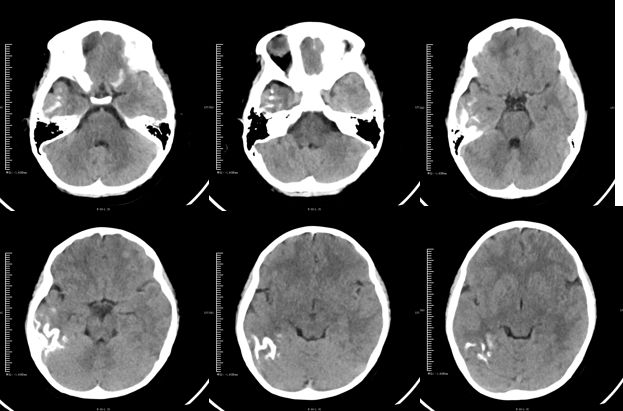

病例8

患者,男,60岁,以"被发现不省人事7小时" 为主诉入院。查体:(呼吸机辅助呼吸)浅昏迷,急性面容,双眼向右侧凝视,双瞳孔直径约3mm,对光反射存在,四肢肌张力偏高,双侧巴氏征阳性。

答案:低血糖脑病(HE)。

补充资料:急诊测血糖2.4mmol/L。低血糖脑病(HE)是一种代谢性脑病,病因是血糖极低,该病发病迅速,症状包括反应迟钝,精神恍惚,行为异常。若患者未得到及时的治疗,症状会在短时间内恶化,患者可能出现嗜睡甚至昏迷。HE有很强的区域选择性,主要侵犯海马、大脑皮质、基底节区、胼胝体压部和皮质下白质,而小脑和脑干很少受累,部分患者发现早,病变可逆,广泛大脑皮质受损者预后差。上期就总结皮层 “缎带征”,多见于如下疾病:低糖高氨上吊死;疯牛病脑偏头疼;假酒中毒持续抽;一氧化碳来凑数;低钠渗透髓鞘脱。